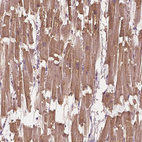

Immunohistochemistry analysis in human heart muscle and pancreas tissues using HPA014305 antibody. Corresponding MYOM1 RNA-seq data are presented for the same tissues.